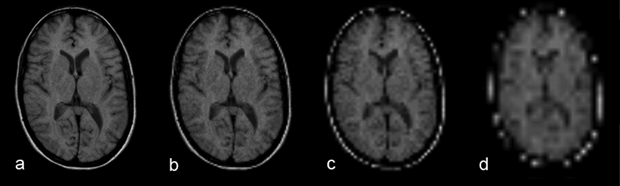

Figure 09-05:

Spatial resolution and partial volume effects: matrix size (a) 256×256, (b) 128×128, (c) 64×64, and (d) 32×32. Due to the partial volume effects, anatomic details disappear.

Simulation software: MR Image Expert®

However, the bigger the voxel size, the better will be the signal (and signal-to- noise). In general, the signal-to-noise is the determining factor for the final voxel-ver­sus-pixel size.